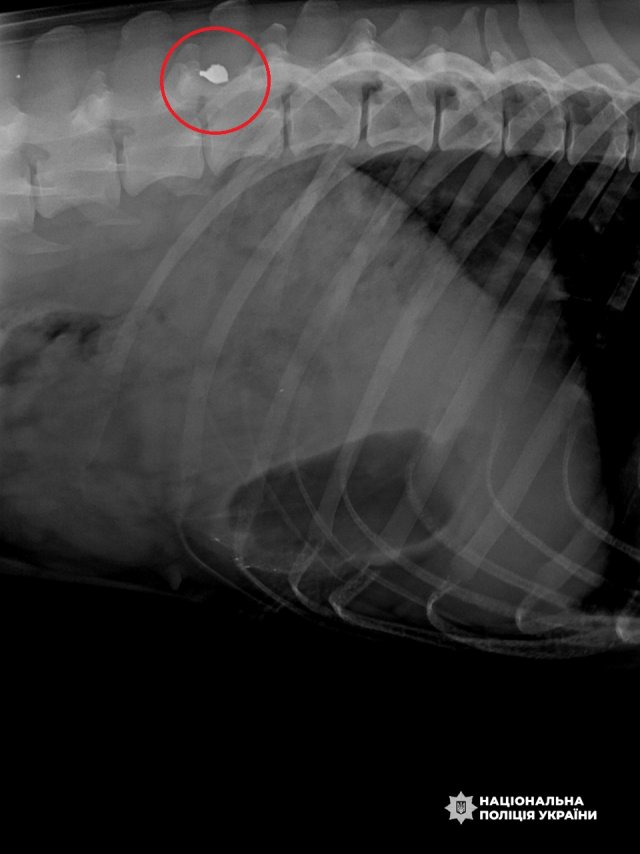

Під час одного з чергувань на блокпосту поліцейський із собакою потрапили під атаку ворожого FPV-дрона. Олег накрив собою пса і таким чином прийняв основний удар на себе. Обидва отримали поранення, та після лікування й реабілітації поліцейський і його вірний напарник знову в строю. Вони щодня виконують завдання, не втрачаючи віри у перемогу та силу своєї справи. Їх історія – приклад справжнього партнерства, вірності та мужності навіть у найнебезпечніших умовах.

Одного разу під час служби на блокпосту поліцейський та Фані потрапили під атаку ворожого FPV-дрона. Вибух пролунав поруч із бліндажем, куди вони ледь встигли забігти – обидва дістали поранення.